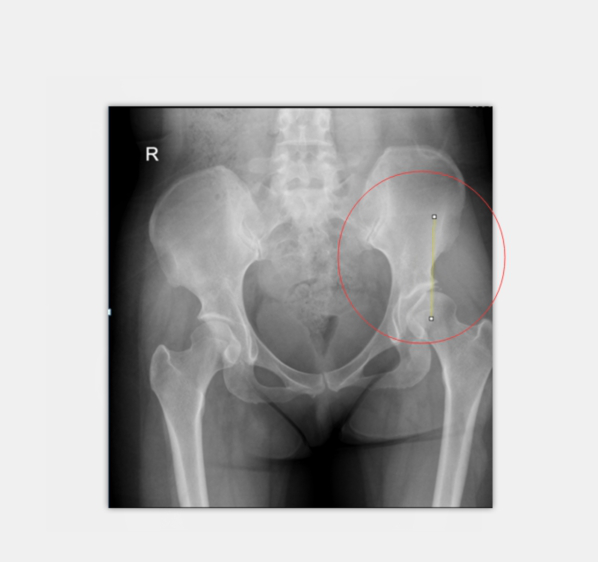

術(shù)前X光:患者左髖臼CE角約0度

診斷考慮:先天性髖臼關(guān)節(jié)發(fā)育不良

術(shù)后X光:CE角約26度,髖臼尺度正常